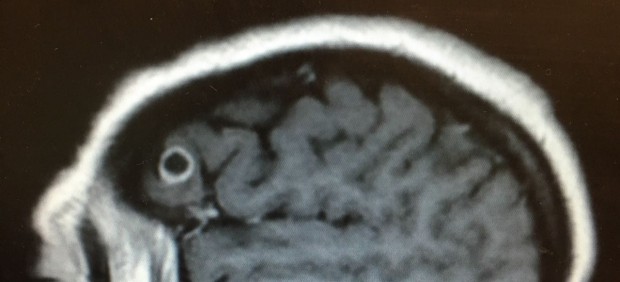

Rachel Palma sufría de insomnio y parálisis en algunas partes del cuerpo. La mujer neoyorquina de 42 años tenía problemas para hablar y recordar las palabras. Los médicos, después de realizarle una resonancia magnética, concluyeron que tenía un tumor cerebral.

Primero, detectaron un elemento que se parecía a una roca o un huevo de codorniz. Después, colocaron un microscopio en la zona afectada. Entonces, encontraron el parásito incrustado en el cerebro, según informó Live Science.